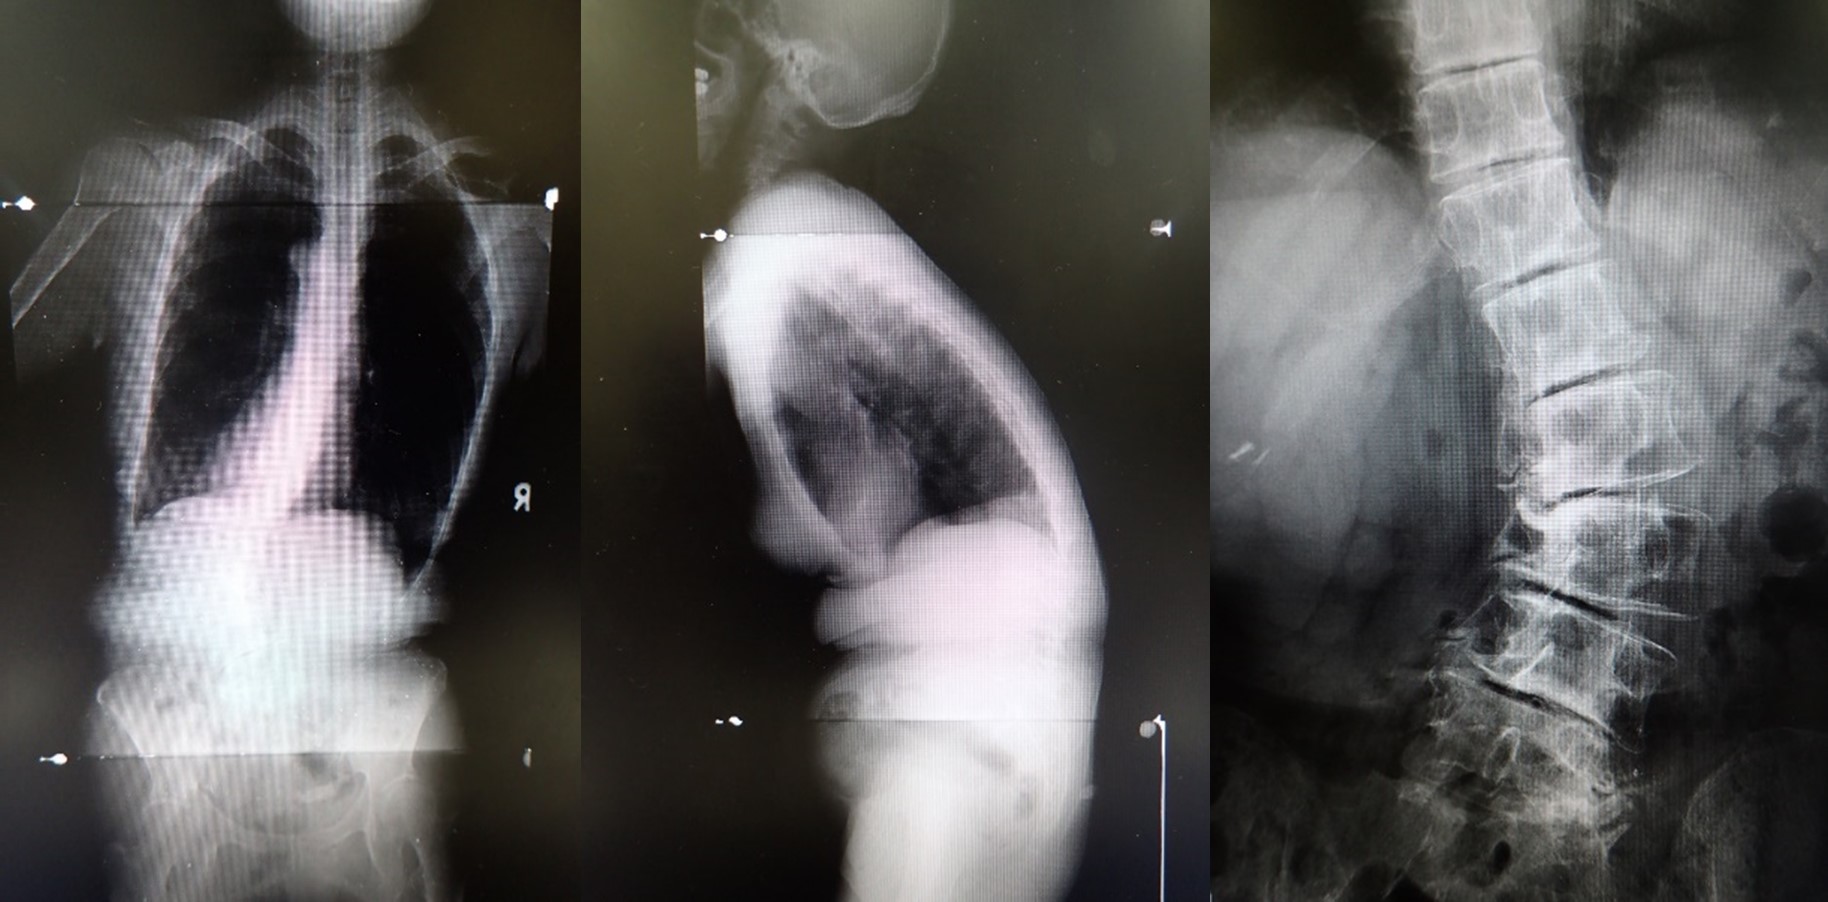

腰椎変性側弯(後弯)症とは、椎間板や椎間関節といった脊椎を構築する組織が傷んだり、骨折による変形などで脊椎が弯曲してくる状態のことです。若年期の特発性側弯症が進行するタイプもありますが、多くは中年期以降の加齢性変化が原因で発症します。

症状は主に腰痛ですが、変形した骨などが神経を圧迫すると、下肢の痛みやしびれ、筋力低下などの神経症状を伴うことがあります。変形が著しくなると体幹のバランスを保てなくなり、杖などの支えが必要な状態となります。

治療は、症状が軽度であれば、薬物治療やコルセット、運動療法などの保存治療が中心になりますが、支えがないと立てない、歩けない、あるいは強い痛みで日常生活が著しく制限されている場合などには手術治療を考慮します。手術は、変形を大きく矯正する必要がある場合には、人工スペーサーや金属性のスクリューなどを用いて、長い範囲の固定を行います(矯正固定術)。また、変形矯正を目的とせず、痛みの原因となっている神経症状の改善を目的とする場合には、圧迫されている神経の周囲を削るのみ、あるいは最も変形の強い範囲に限局した短い範囲の固定術で経過をみることもあります。腰椎変性側弯(後弯)症の手術は、一般的に体にかかる負担が大きく、高い技能を求められる手術です。